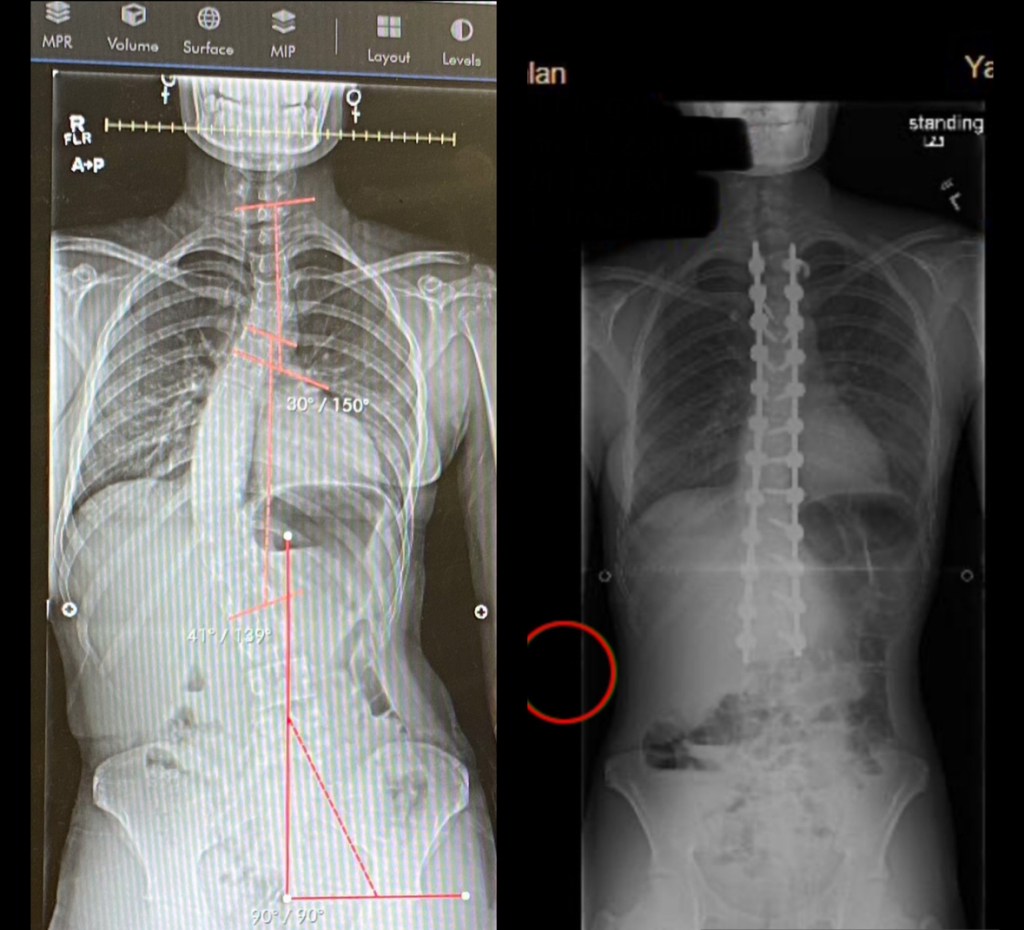

In the fall of 2023, I found out I would need scoliosis surgery to correct a 41% curvature in my spine. When it came time to schedule the surgery, I was given two options by my medical team: YNNH or another hospital slightly further away but with a great reputation for working with pediatric cases like mine. Being more familiar with YNNH and its overall positive reputation, it gave me a certain element of comfort, especially knowing my surgery and post-surgical care would take place at the Children’s Hospital. For those reasons, my family and I opted for YNNH over the other facility and I am grateful I made that choice.